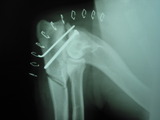

- Proceso ancóneo no unido: La técnica más fiable (90% de éxitos) es la fijación con tornillo y osteotomía cubital proximal dinámica ( un pequeño corte en el cúbito) ( ver foto)